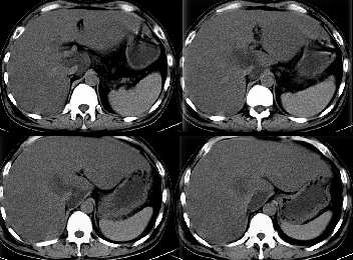

脂肪肝,尾状叶脂肪浸润明显.其他好象没问题?

支持1脂肪肝。2胆囊炎。3黄疸、肝大、转氨酶升高为正常值之20倍。考虑重症肝炎可能。

重度脂肪肝,胆囊炎。至于病毒性肝炎需实验室检查才能诊断。

重症性肝炎,肝密度普遍是肝细胞肿胀改变,不好确定脂肪肝。

1:肝左叶病灶比较明显,似有包膜,动脉期病灶内有不规则片样强化,支持肝癌诊断。2:肝脏增大,密度明显减低,且转氨酶明显升高,应考虑急性肝炎。本人认为:(1)急性肝炎,(2)肝左叶肝癌。

临床消瘦体重剧减,支持恶变质,失代偿表现。结合ct征象:肝体积明显增大,支持重症肝炎;左叶及尾叶低密度病灶,支持合并有恶性变可能,其它方面不太好解释低密度的由来

1)肝左叶肝癌2)全肝癌?重症肝炎?本人曾经遇到一例全肝癌,如本病例图像表现。期待结果。